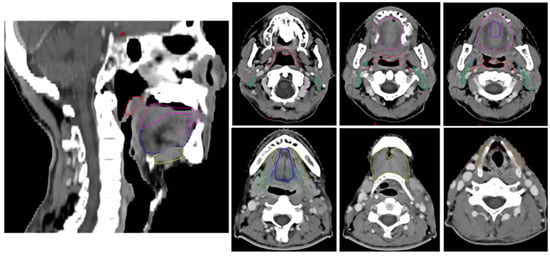

Background/Objectives: Financial toxicity (FT) refers to the financial burden directly or indirectly caused by a patient’s medical care. Patients with head and neck cancer (HNC) are particularly vulnerable to FT due to lower rates of return to work and higher out-of-pocket payments

Background/Objectives: Financial toxicity (FT) refers to the financial burden directly or indirectly caused by a patient’s medical care. Patients with head and neck cancer (HNC) are particularly vulnerable to FT due to lower rates of return to work and higher out-of-pocket payments (OOPP). In this cross-sectional study, we assessed the amount and types of OOPP, as well as the prevalence of FT, in HNC patients who had completed curative radiotherapy. Methods: We included HNC patients who underwent curative-intent radiotherapy at four private clinics in Romania, within 12 months of completing treatment. Participants completed a 25-item questionnaire capturing sociodemographic information, insurance status, income, and OOPP. To assess subjective FT, we used the validated nine-item Financial Index of Toxicity (FIT), which measures three FT domains: financial stress, financial strain, and lost productivity. Each domain and the total score range from 0 to 100, with higher scores indicating greater financial toxicity. Descriptive statistics were used to summarize patient characteristics. Pearson’s chi-square, t-tests, and one-way ANOVA were used to assess statistical associations, with a significance threshold of p < 0.05. Results: Among 113 patients (mean age: 59), the majority were male (74.3%) and married (74.3%), with 40% having completed university or higher education. The most frequent tumor sites were the oropharynx (29 cases), larynx (22), and oral cavity (21). Concurrent chemoradiation was the most common treatment modality (47%). The mean total FT score was 18.8. Overall, 39.8% of patients experienced financial toxicity, and 29.2% scored above the mean in financial stress. Moderate financial strain (score > 21) was reported by 39.8% of participants, and approximately one-third reported loss of productivity. Transportation and nutritional supplements were the most common OOPP categories. Notably, 42% of patients spent at least 400 euros—equivalent to Romania’s monthly minimum income—on transportation during radiotherapy. FT was significantly associated with employment and marital status, but not with tumor site or treatment type. Conclusions: Among Romanian HNC patients treated with curative radiotherapy, we found substantial OOPP, particularly for transportation and nutritional supplements. While overall FT levels were moderate, divorced patients and those retired due to other chronic conditions were the most vulnerable to financial distress. Financial toxicity can directly affect treatment adherence, survival, and quality of life. By integrating financial counseling, social support, and broader coverage of treatment-related expenses, healthcare systems can mitigate FT for these patients.